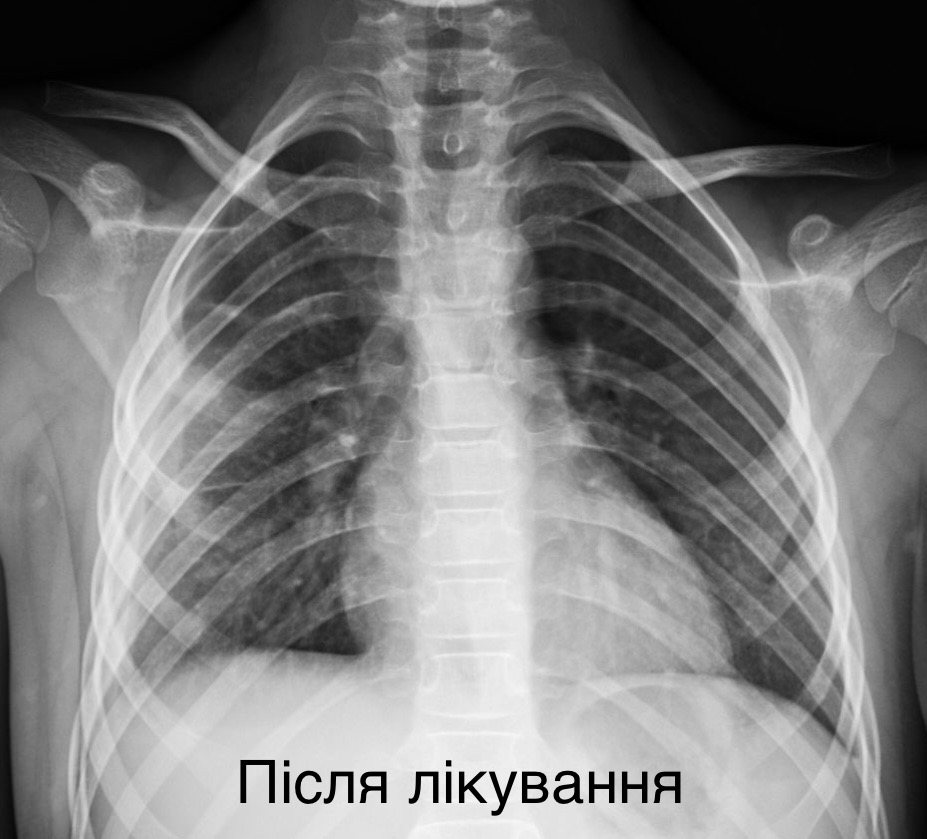

Львівські хірурги врятували 7-річну дівчинку з важкою деструктивною пневмонією

Лікарям вдалося зберегти уражену легеню, зробивши два розрізи розміром менше одного сантиметра

У Львові медики врятували життя дитини, яку екстрено доставили у критичному стані з деструктивною пневмонією правої легені. Дівчинка була у важкому стані: мала високу температуру тіла, задишку та низьку сатурацію кисню у крові. Про це повідомила Лікарня “Охматдит” у п’ятницю, 21 листопада.

7-річну пацієнтку одразу госпіталізували до клініки торакальної хірургії. Медики розпочали інтенсивну терапію, призначивши два сильні антибіотики, інфузійну та кисневу підтримку. Медична команда виконала тораскопічну операцію — малоінвазивне втручання, яке дозволило зберегти легеню.

“Лише через 2 розрізи розміром до 1 см ми дісталися до ураженої легені, усунули гнійно-некротичні вогнища і зберегли легеню”, — зазначив торакальний хірург Олександр Колодій.

Зараз дівчинка самостійно дихає та активно відновлюється.